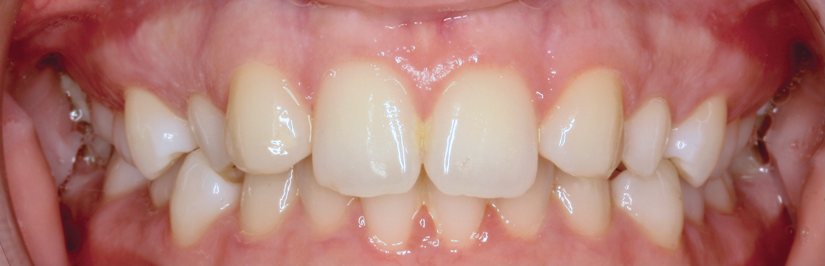

Canine substitution can be an excellent alternative for the replacement of the missing maxillary lateral incisor (Figure 1 and Figure 2). This treatment option can be particularly effective if the canine has a flat facial surface, is not too wide mesiodistally, and has a color similar to the contralateral lateral incisor. Patients with missing lateral incisors who present with maxillary dentoalveolar protrusion and/or an Angle class II molar relationship and minimal crowding in the mandibular arch are considered excellent candidates for canine substitution.7

Fig 1. Patient was missing teeth Nos. 7 and 10 (Fig 1). Canine substitution was the treatment used to replace these missing teeth (Fig 2).

Figure 1

Fig 2. Patient was missing teeth Nos. 7 and 10 (Fig 1). Canine substitution was the treatment used to replace these missing teeth (Fig 2).

Figure 2